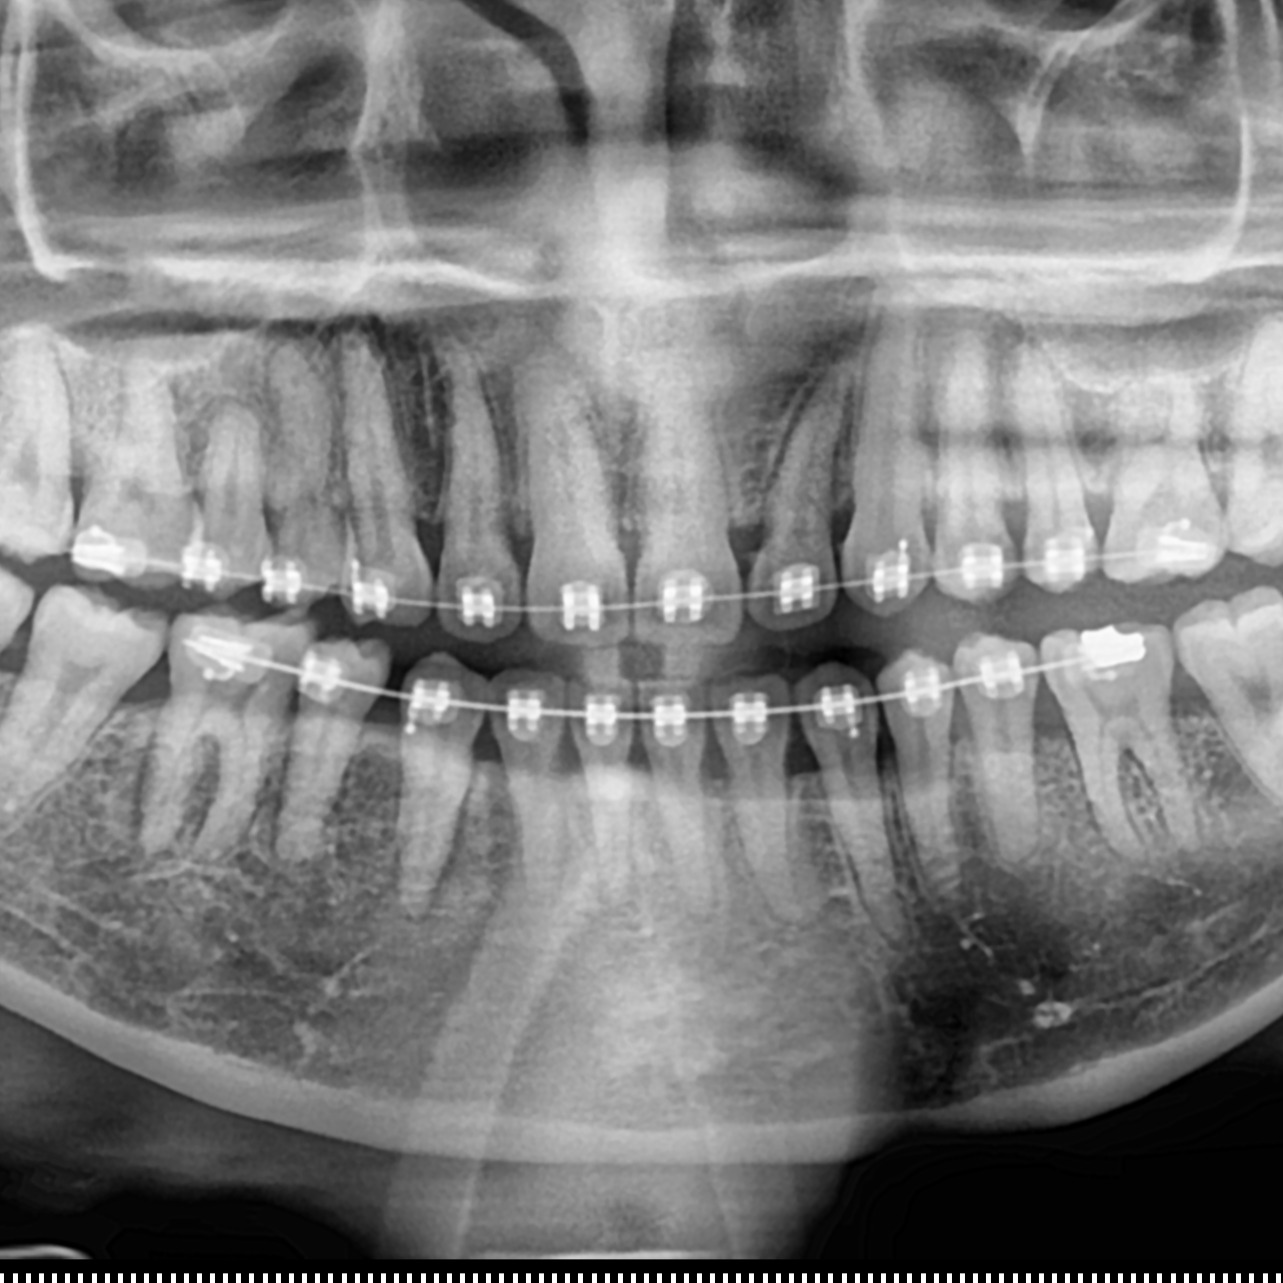

Hidup di Malaysia Sebagai Dokter Gigi, Suami dan Ayah

Sharing kehidupan dan hikmah hidup sebagai dokter gigi, Suami dan Ayah